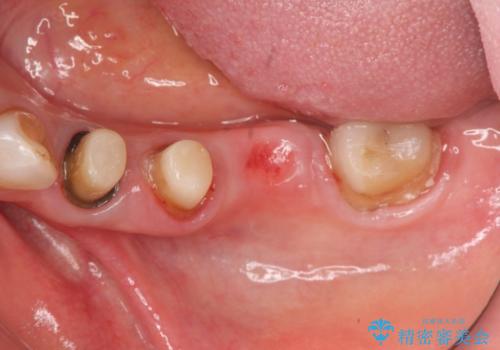

- 古くなり黒ずんできたブリッジのやりかえを希望され来院されました。

老朽化した銀パラジウム合金のブリッジを除去し、ジルコニア製のブリッジでやりかえを計画します。